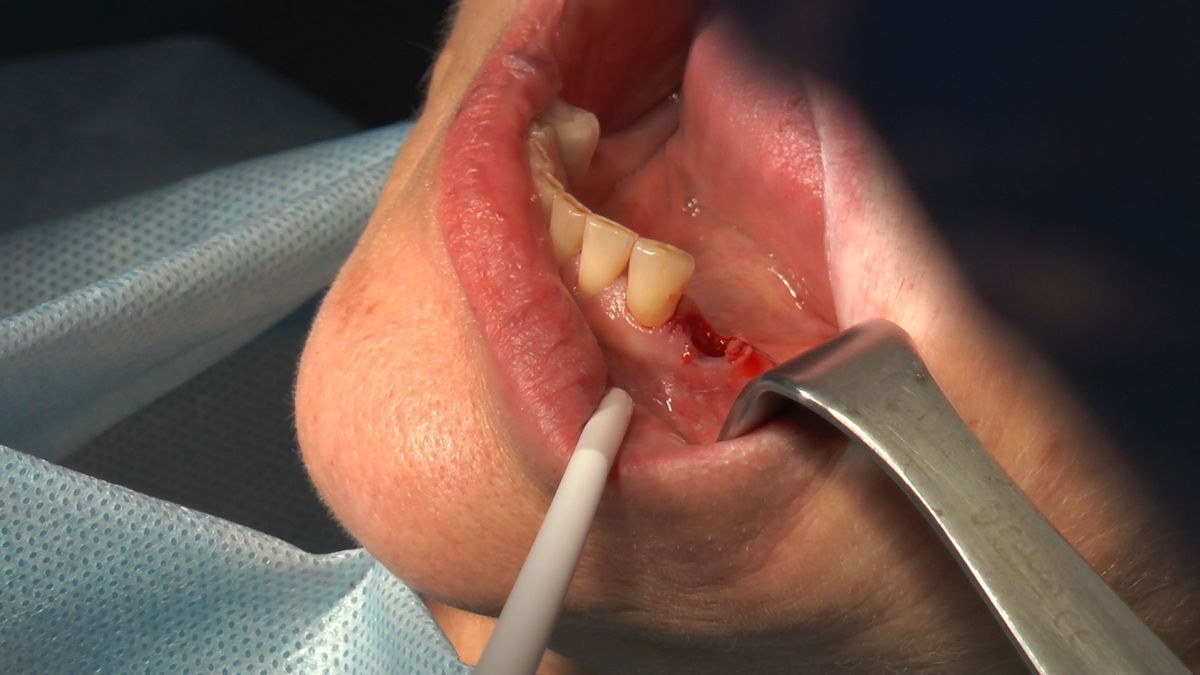

W ostatni weekend czerwca 2018 roku kursanci II Sezonu Preludium Implantologii odbyli piątą, finałową sesję, która w całości podporządkowana była praktyce. W ciągu dwóch dni zabiegowych Lekarze uczestniczący w szkoleniu przeprowadzili szereg zabiegów pod kierunkiem dr n.med. Violetty Szycik. Wszczepili 17 implantów oraz przeprowadzili ekstrakcje i zabiegi regeneracyjne kości. Zabiegi były wykonywane także w sedacji dożylnej z udziałem specjalisty anestezjologii i intensywnej terapii dr Jolanty Grzybowskiej. Preludium implantologii to nowy program edukacyjny dla adeptów implantologii stomatologicznej, którego celem jest wprowadzenie do implantologii poprzez pozyskanie wiedzy w szerokim zakresie i uwzględnieniem szczegółów mających decydujące znaczenie dla powodzenia leczenia implantologicznego. Ale tak jak wszystkie szkolenia w Instytucie Vivadental, w tym wiodące Practiculum Implantologii, zorientowane jest na praktyce i samodzielnym wykonywaniu zabiegów pod kierunkiem Mentora. To najlepsza edukacja w medycynie zabiegowej, a zarazem najlepszy start do implantologii.